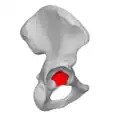

Тазовые кости в скелете таза человека выделены красным